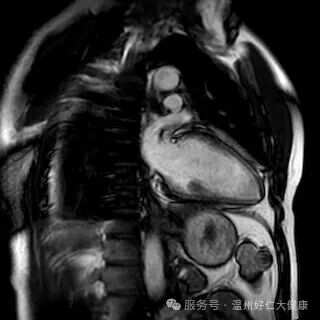

针对心脑血管早筛的核心需求,我院全力推进冠脉磁共振检查技术普及,凭借无创、无辐射、不打造影剂的硬核优势,攻克传统筛查的痛点,成为不同人群冠脉血管筛查的优选方案,让早期血管病变无所遁形:无创安全,适配全人群:全程无需插管、不注射造影剂,从根源规避造影剂过敏、肾脏代谢负担等问题,肾功能不全、备孕、造影剂过敏等特殊人群也能安心检查,真正实现 “零负担筛查”; 零辐射高精准,捕捉隐匿病变,无任何电离辐射,即使多次复查也不会对身体造成损伤;成像精度可清晰识别冠脉血管软斑、硬斑等斑块性质,精准判断血管狭窄程度,哪怕是早期隐匿的微小病变,也能精准检出; 一站式筛查,兼顾血管与心脏:不仅能排查冠脉血管病变,还能同步评估心肌灌注、心脏收缩舒张功能,清晰呈现心肌细微结构,一站式完成 “血管 + 心脏” 全面检查,为冠心病早期筛查、高危人群动态监测提供精准的诊断依据。